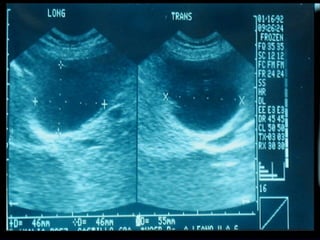

SONOGRAMA ABDOMINAL EVACUACIÓN VESÍCULA BILIAR Estructura elongada, ovoide Pared bien definida, no debe superar los 3 mm. De grosor. Longitud 7 -10 cm. (menos de 13 cm.) Diámetro  3 cm. ( < 4 cm. )

SONOGRAMA ABDOMINAL PATOLOGIAS DE VESÍCULA BILIAR LITIASIS VESICULAR Cuando miden 3 mm de ven en la ecografía (certeza del diagnóstico por U.S.  del 96% ) Eco brillante, definido en el interior de la luz vesícula móvil y asociado  con sombra acústica posterior.

SONOGRAMA ABDOMINAL EVALUACIÓN COLECISTITIS AGUDA Inflamación de la vesícula biliar   Litiasis vesicular, 5 % colecistitis es alitiásica. Pared anterior mayor de 3 mm. Murphy ecográfico positivo Edema, halo hipoecoico alrededor de la pared Distensión de la vesícula (70 ml. O más)